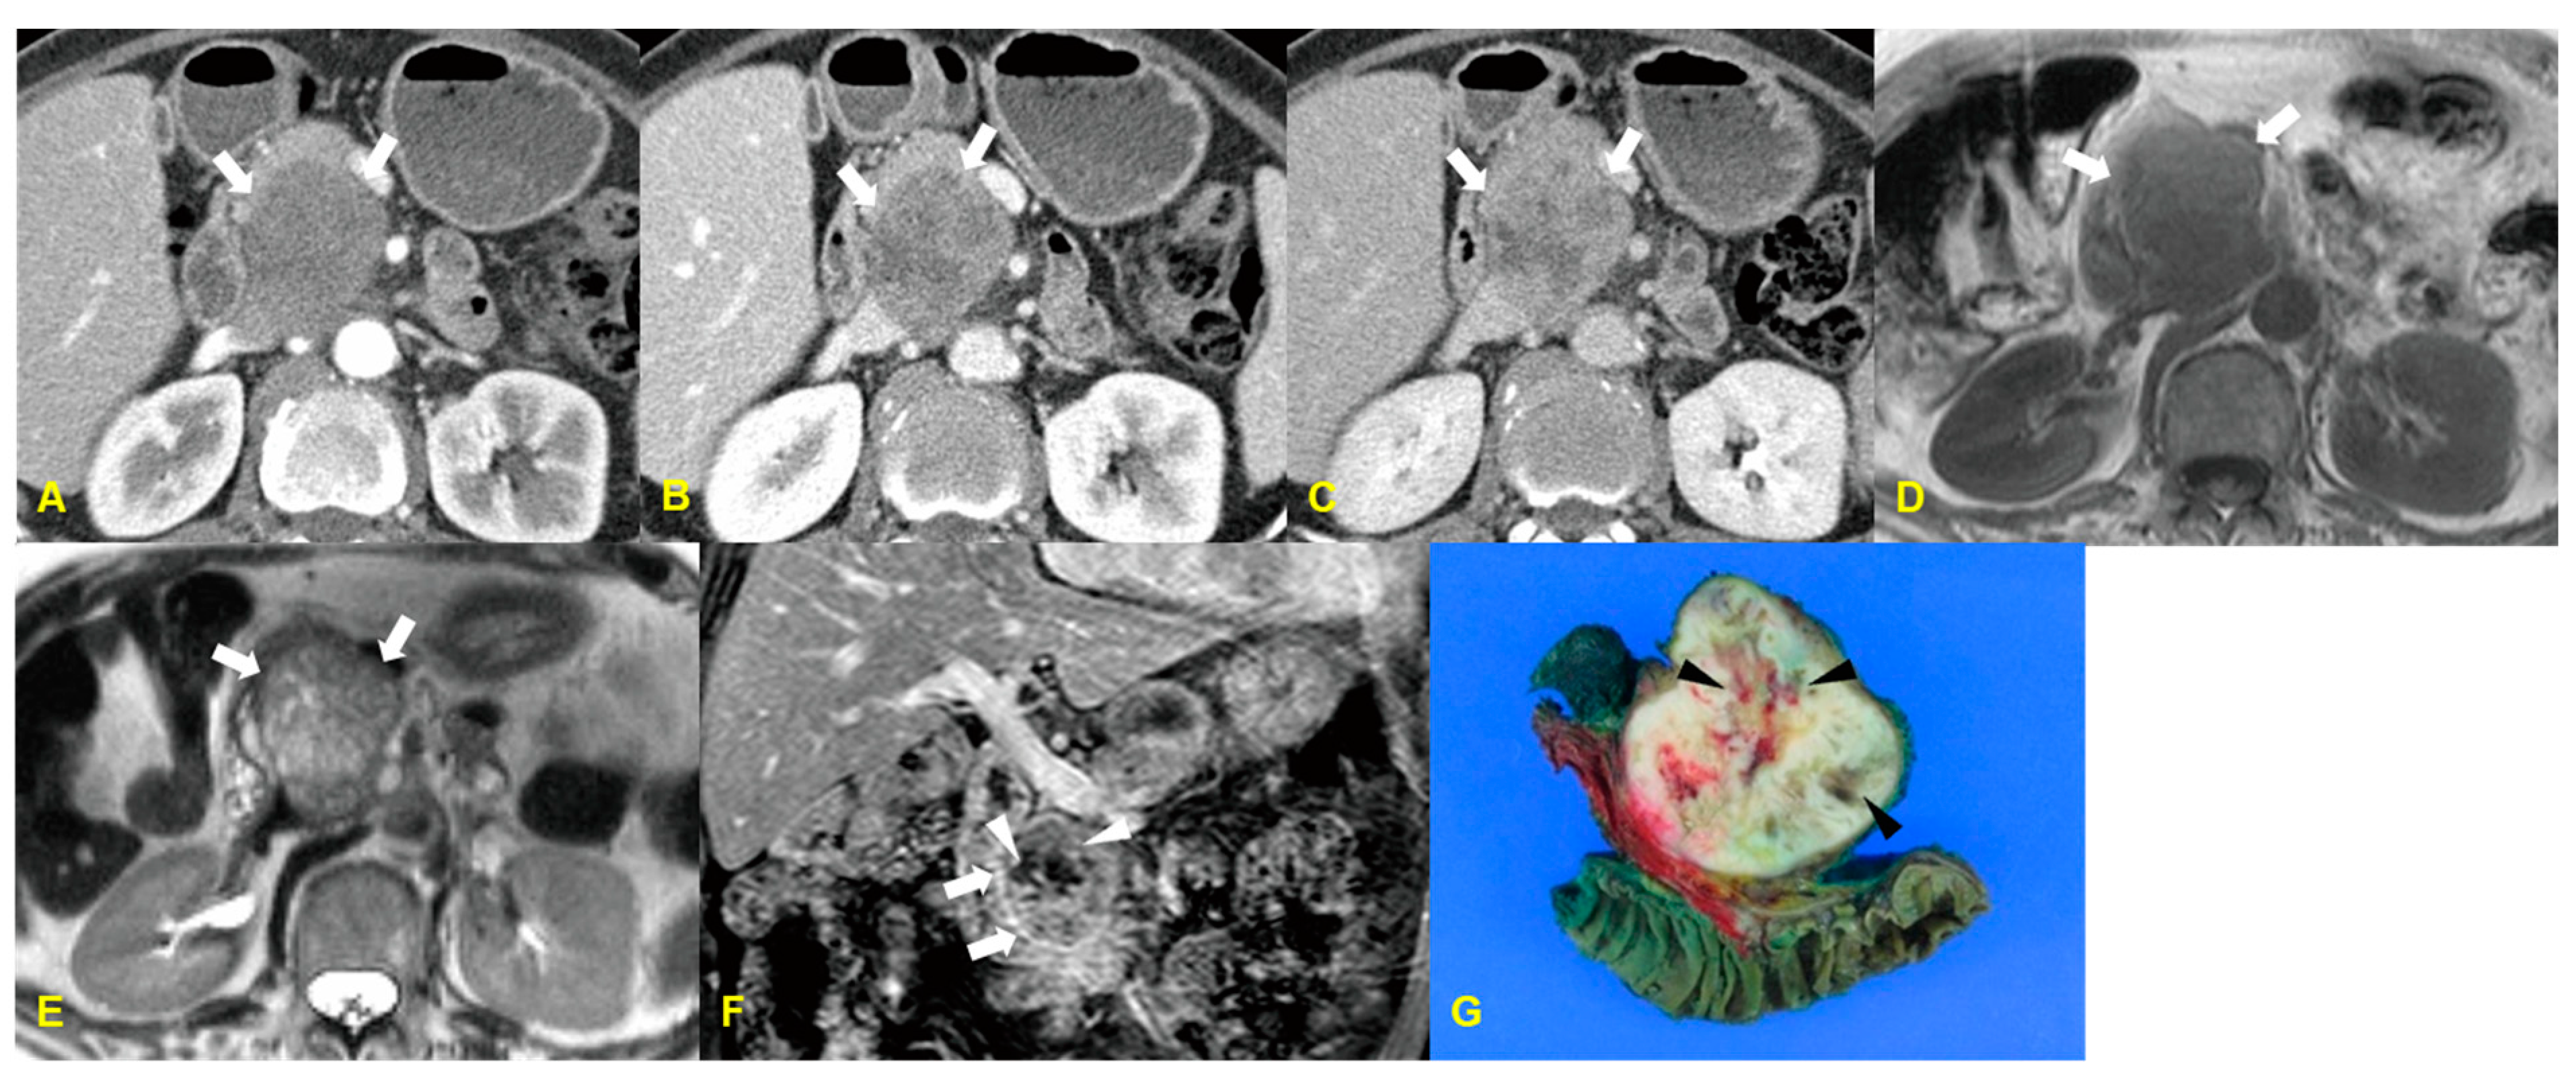

10. Infarcted Intrapancreatic Accessory Spleen

10.1. Imaging Finding

10.2. Differential Diagnosis

| Infarcted intrapancreatic spleen | Enhancement pattern: poor enhancement/ Sometimes, peripheral enhancement by capsular vessels |